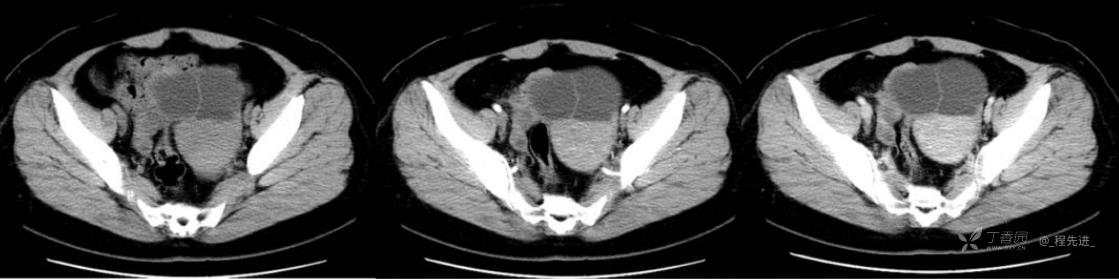

1月特别精彩病例|中老年女性,盆腔包块近半年持续增大【病理已公布】

患者年龄:53岁

简要病史:4年前体检时发现盆腔包块及子宫肌瘤,近半年复查盆腔彩超发现包块持续增大,近1年月经欠规律,伴腰、腹胀。

体格检查:宫颈举痛(+),子宫增大,质地中等,活动可,无压痛;右下腹轻压痛,无反跳痛,左侧附件区未扪及明显包块,无压痛。

阴式彩超:子宫约65*58*44mm大小,子宫肌层可见多个低回声块影,较大的为35*27mm(位于子宫前壁下段偏右侧壁),边界清,内回声欠均匀,后方回声衰减。考虑子宫多发肌瘤。子宫后壁可见一混合回声包块,大小约31*20mm,边界不清,内呈强弱回声,分布不均,考虑子宫腺肌瘤,其他疾患待删。子宫内膜厚6mm,宫颈可见多个囊性暗区,边界清,内透声好,后壁效应增强,较大的为15*11mm。子宫前方偏左侧可探及一大小89*75mm囊性肿块,边界清,壁薄光滑,内透声好,可见分隔光带